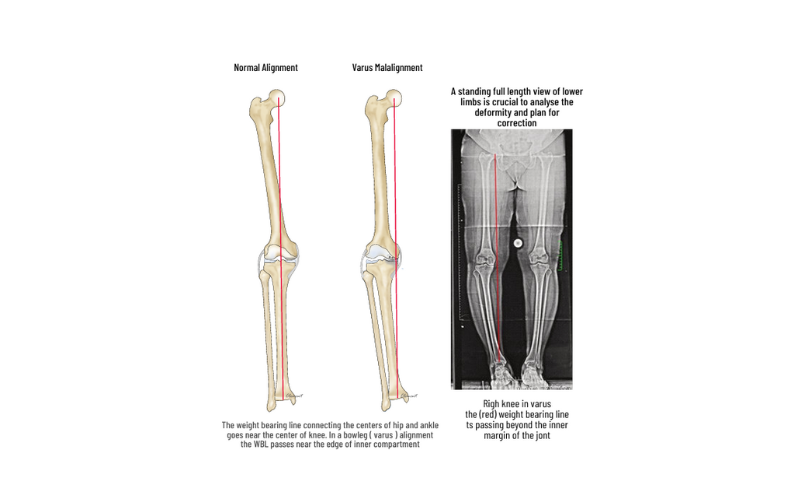

Malalignment

Faulty knee alignment (bow-leg or knock-knee) overloads one compartment, resulting in cartilage injury, meniscus tears and joint space narrowing. As the joint space reduces, the alignment also worsens leading to a vicious cycle of joint destruction and deformity. Fortunately correction of the alignment at an early stage can restore knee function and postpone joint replacement

HTO-High Tibial Osteotomy

HTO is a procedure to correct the alignment and redistribute the load to the non-involved compartment. Arthroscopy is performed to assess the status of the joint and to treat meniscal tears, loose bodies, and cartilage tears. Based on preoperative planning and using precision instrumentation, a partial bone cut (osteotomy) is made in the upper tibia and is slowly opened to the desired level to shift the load to the normal compartment. The osteotomy is fixed with strong PEEK or titanium plates to allow early movements and weight-bearing. HTO also protects procedures like meniscus repair and cartilage repair by unloading the joint. HTO can postpone the need for knee replacement for many years.